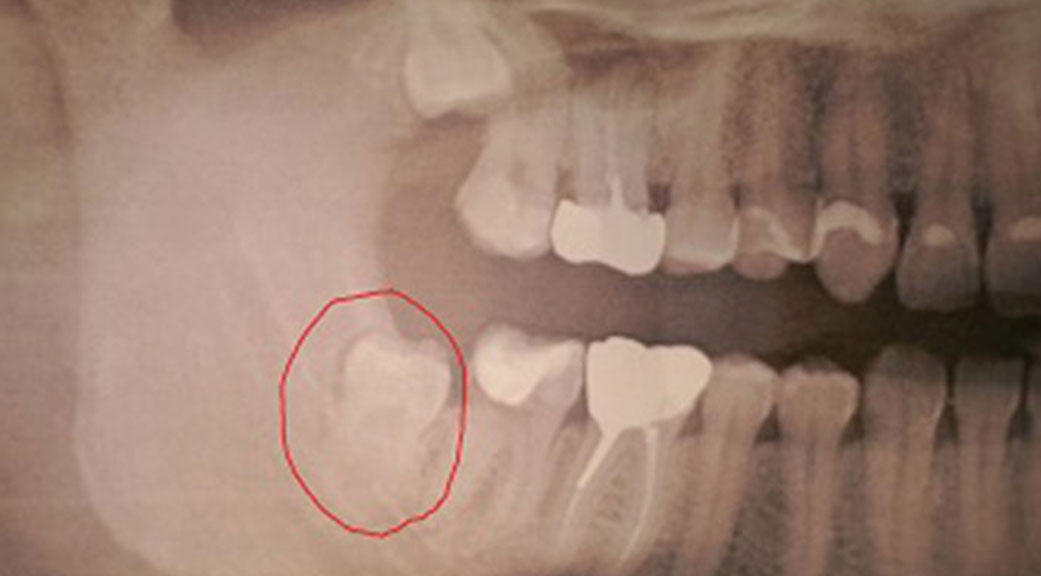

Dents de sagesse